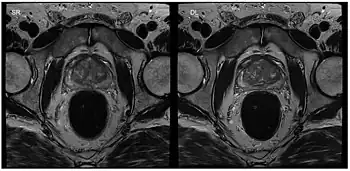

Musculoskeletal MRI

Apart from cardiac MRI other real-time applications deal with functional studies of joint kinetics (e.g., temporomandibular joint,[29] knee and the wrist[30]) or address the coordinated dynamics of the articulators such as lips, tongue, soft palate and vocal folds during speaking (articulatory phonetics)[31] or swallowing.[32] Musculoskeletal imaging in particular benefits from real-time observation. Researchers at the NYU Grossman School of Medicine[33] developed a RT-MRI glove for imaging movement of the hand. The glove uses high impedance coils to prevent the generation of eddy currents from rapidly changing magnetic fields and bSSFP for rapid imaging times. High-impedance coils remove the need for specific coil conformations and active gradient shielding.[34]